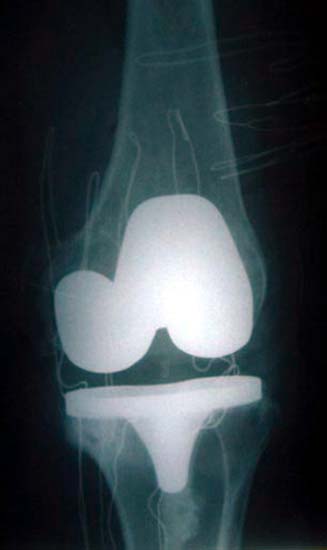

图:切除磨损破坏的关节面,安装平滑的人工关节面,组成新关节

为患者行一期双膝置换术,X线片显示假体位置好,下肢力线恢复。

患者女性,56岁,双膝骨关节炎15年,双膝屈伸受限,下蹲困难。线片显示膝骨关节炎改变,关节间隙已经消失。膝内翻畸形。行分期人工膝关节置换术。